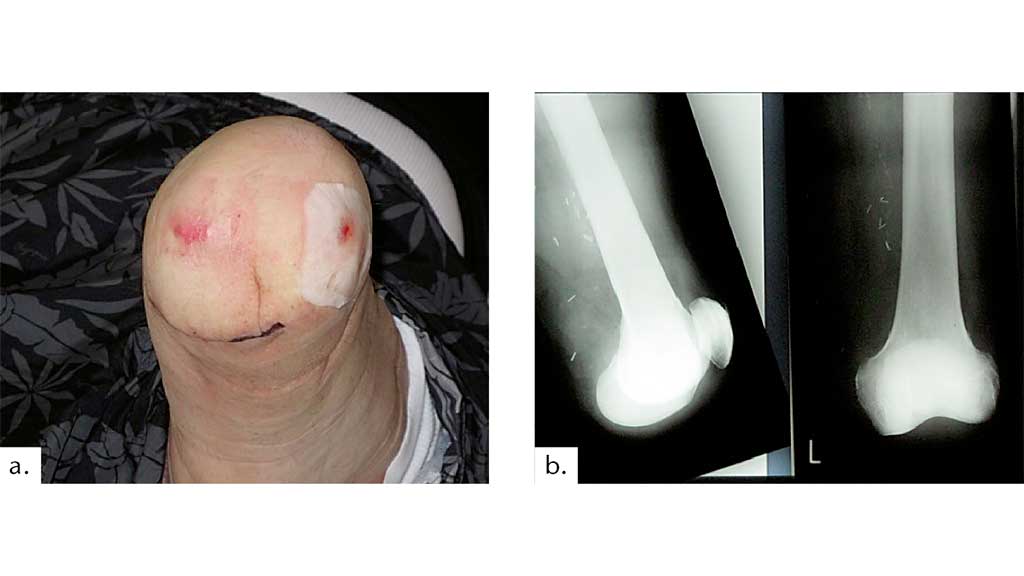

Ein Dekubitus im Bereich der Femurkondylen durch postoperativ falsche Lagerung und zu enge Wickelung (Abb. 10) führt zu einer unnötigen prolongierten Rehabilitation eines an sich kurz nach der Amputation voll gehfähigen Patienten.